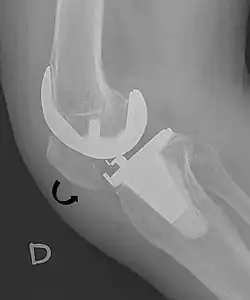

For recurrent patellar dislocations or cases with chronic instability, surgical intervention may be necessary. Patella stabilization surgery aims to restore proper kneecap tracking and reduce the risk of future dislocations.[4] Surgical options include reconstruction of the medial patellofemoral ligament (MPFL), realignment procedures such as osteotomy, and soft tissue adjustments around the patella.[4] MPFL reconstruction typically involves harvesting a hamstring tendon, commonly the gracilis, to create a new ligament that is positioned anatomically and secured with suture anchors.[4]

- ^ Melloni, Pietro; Veintemillas, Maite; Marin, Anna; Valls, Rafael (2013). "Imaging Patellar Complications After Knee Arthroplasty". Arthroplasty - Update. doi:10.5772/53666. ISBN 978-953-51-0995-2. (CC-BY-3.0)